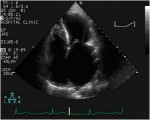

Annulus-speziale.jpg

Forma a sella dell’anulus mitralico